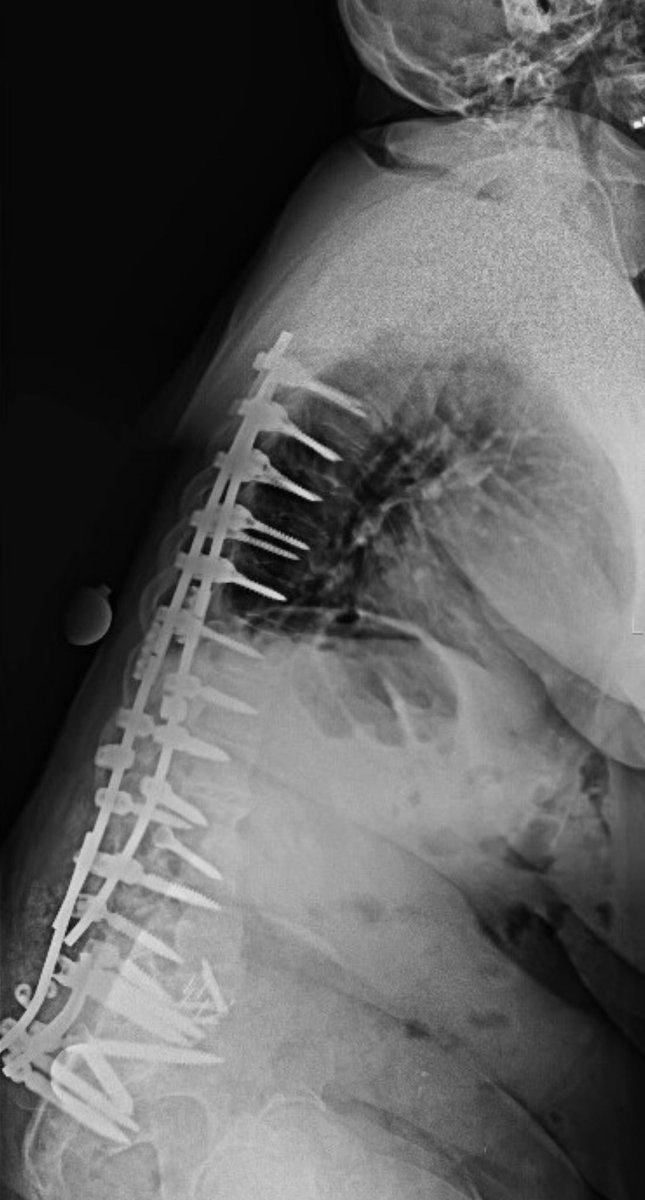

Excited to be featured on this Neuro Pathways Podcast episode discussing diagnosis and intervention of idiopathic scoliosis! #scoliosis #spinesurgery @CleClinicNS @ClevelandClinic podcasts.apple.com/us/podcast/neu…

ABNS Board Certified Neurosurgeon, Assistant Professor CWRU. Complex Spine Deformity, Spine Oncology, Scoliosis. Follower of Christ. Tweets are my own.